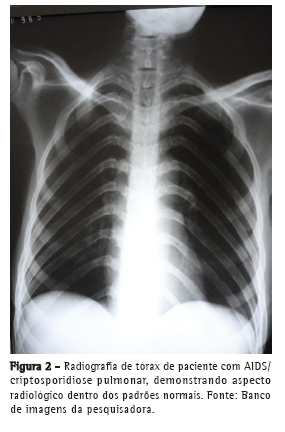

Em uma pesquisa conduzida em hospitais de referência para atendimento de pacientes com HIV/AIDS e suspeita clínica de tuberculose pulmonar em Recife (PE), de um total de 130 exames de escarro realizados até o momento, Cryptosporidium spp. foi o único agente identificado em 2 (1,5%) daqueles pacientes; o diagnóstico foi realizado através da identificação de oocistos de Cryptosporidium spp. no exame de escarro corado com Ziehl-Neelsen (Figura 1). Em ambos os casos, os pacientes apresentaram febre vespertina, tosse, perda ponderal e mal-estar geral, sugerindo o diagnóstico de tuberculose pulmonar. Nos 2 casos estudados observou-se um grave comprometimento imune, com contagem das células T CD4 muito baixas (25 e 37células/µL). Apesar de não ter sido pesquisada a presença de Pneumocystis jirovecii, foi prescrito sulfametoxazol/trimetoprima para a profilaxia contra esse agente. Ambos os pacientes tiveram diagnóstico recente de AIDS, e apenas 1 deles teve suspeita clínica inicial de criptosporidiose intestinal, confirmada através do exame coproparasitológico, enquanto o outro apresentou sinais clínicos sugestivos de tuberculose pulmonar, sem, entretanto, referir queixas digestivas. O exame radiográfico do tórax (Figura 2) foi normal nos 2 pacientes. As culturas de escarro realizadas utilizando-se os meios Löwenstein-Jensen e Middlebrook 7H9 não evidenciaram crescimento de micobactérias.